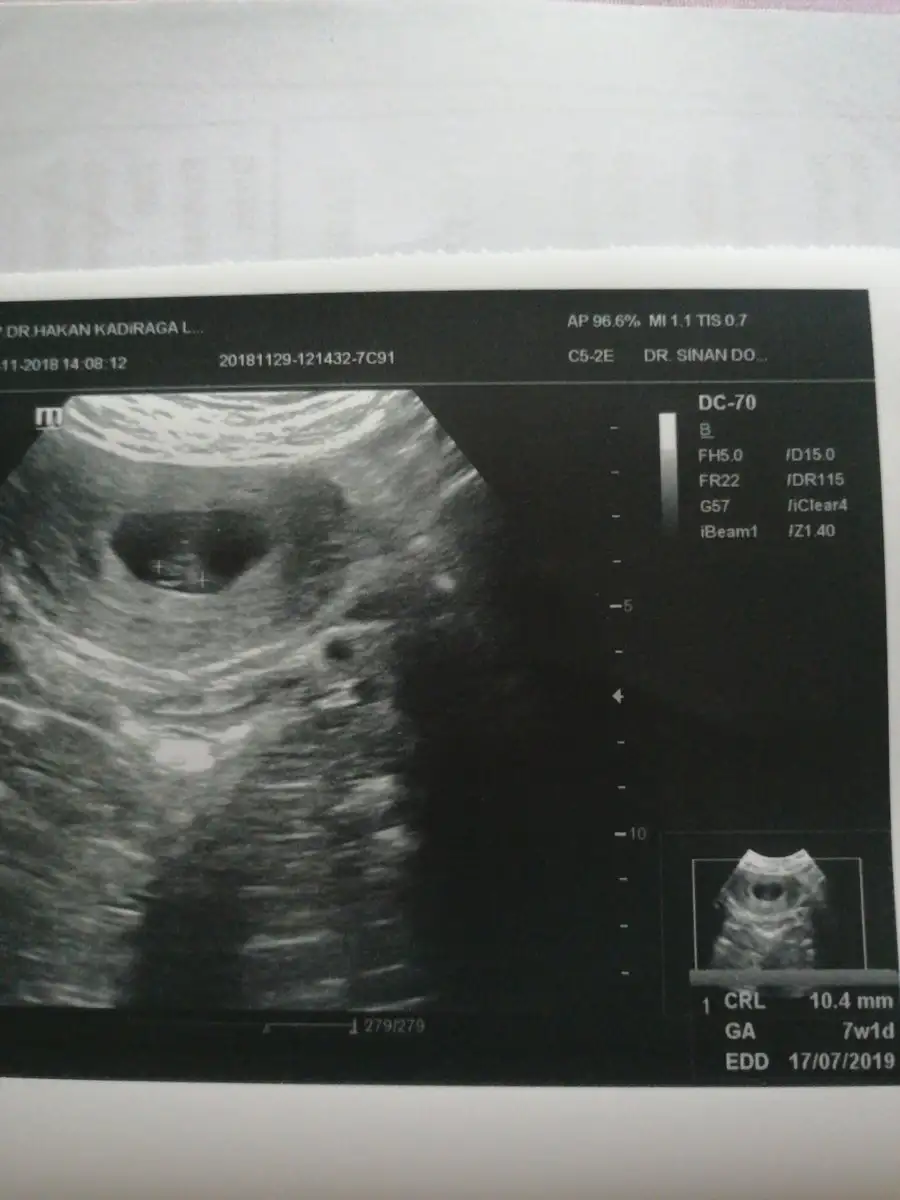

1 cm’i geçmiş 7 hafta 1 günlük görünüyor maşallah kuzucuk. Bekleden doğum tarihide 17 temmuz